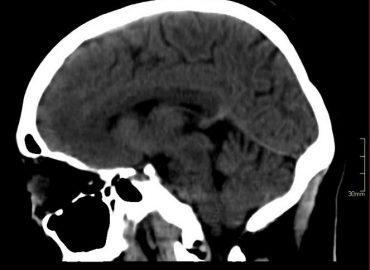

Paciente femenina de 35 años que consulta por mareos y diplopía. APP: hepatitis autoinmune (hace 11 años).